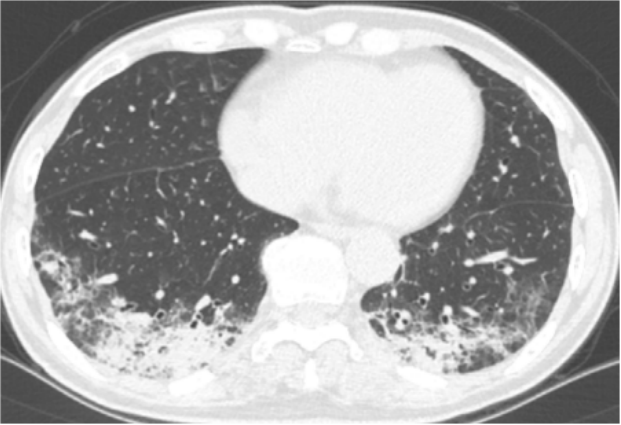

PIV肺炎与其他病原体感染的临床表现不易区分。咳嗽、流涕及咽痛是最常见的症状,特殊表现为犬吠样咳嗽,喘息更常见(86%)。原基础病急性加重也是常见表现(如哮喘、慢阻肺及心衰)。查体哮鸣音比例高(52%),氧疗、插管率及入ICU比例与其他肺炎无显著差别。PIV肺炎住院天数相对较少。PIV肺炎的影像学表现无特异性,与其他病毒性肺炎的表现相似,包括树芽征、间质浸润、磨玻璃影、支气管壁增厚和支气管周围实变。美国一项多中心回顾性门诊调查研究中分析了24例成人PIV感染患者(免疫功能低下占38%)的影像特点【这些患者没有检测到其他病原体,7天内有胸部CT结果】:以气道为中心的分布(67%)【气道中心分布患者例数除以24,但这24例患者中有4例没有肺部感染表现。但个人认为应该用气道中心分布患者例数除以20,结果所得比率为80%】,树芽征(54%)、支气管壁增厚(支气管炎、细支气管炎、支气管肺炎)(图1,图2)显著高于流感病毒(27%)、腺病毒(10%);与呼吸道合胞病毒(53%)相仿(类似的分子结构:副黏病毒科,负单链RNA病毒)。磨玻璃病变(38%)、多灶性实变(25%)(图3)与其他病毒肺炎无明显差别(除外腺病毒),无双肺弥漫性磨玻璃或实变病例,无肺炎比例17%,显著低于流感病毒(43%)。由于绝大多数门诊PIV感染患者症状很轻, 可能完全没有做CT检查, 因此该研究结果仍值得商榷。图1. 一例61岁女性患者,新发呼吸困难所致副流感病毒引起的支气管炎。CT图像显示支气管壁弥漫性增厚。

图源:AJR Am J Roentgenol, 2013, 201(3):550-554.

图2. 一例54岁男性患者,副流感病毒引起的毛细支气管炎,出现咳嗽和发热。CT图像显示轻微的树芽征,伴轻度弥漫性支气管壁增厚。